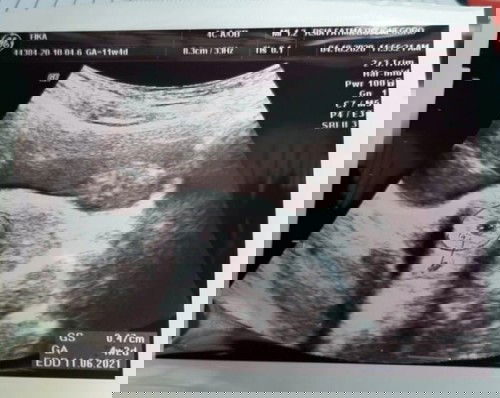

#seriusnanya bun, kemaren saya USG kata dokter sudah jalan 4week, sudah muncul kantong kehamilannya. Tapi saya tespek pagi hari kok selalu negatif ya? Belom pernah saya tes positif. Mana yang lebih akurat tespek/usg??? Saya hamil/gak ya bun?bingung....